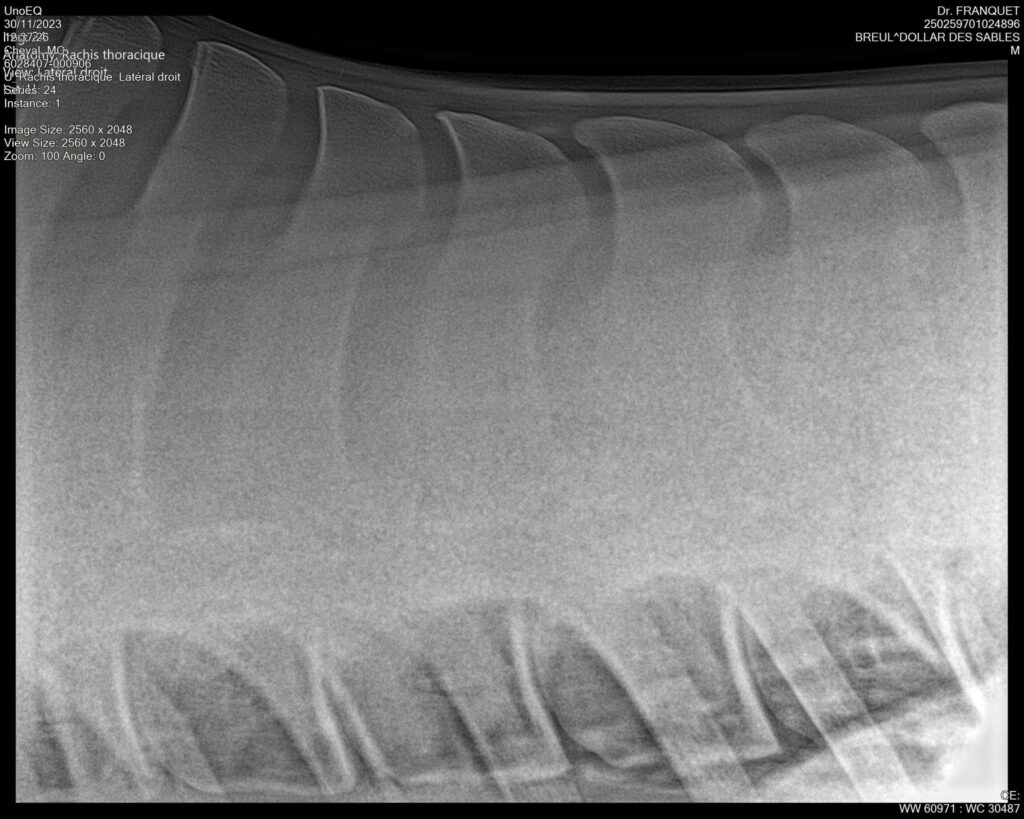

DOLLAR DES SABLES, Selle Français, hongre, 12 ans par DOLLAR DE MURIER x ABKE (ACORADO). Classé 135 avec professionnel à fait 125 avec amateur, récemment classé sur amateur 1GP 120. Très beau modèle ! Gentil cheval, respectueux avec des moyens et du sang. Transport OK, maréchalerie OK, santé RAS, Bilan clichés radios OK.

RADIOS